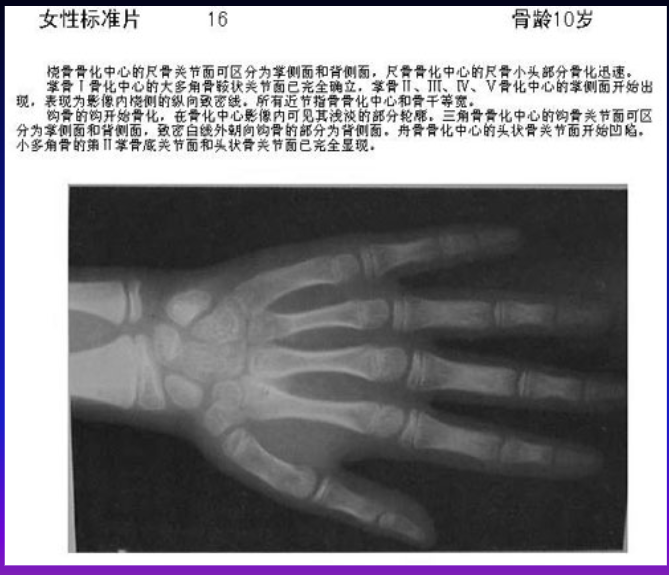

中国儿童标准骨龄片

儿童(女性)骨龄x线图片对照

骨龄x线对照图